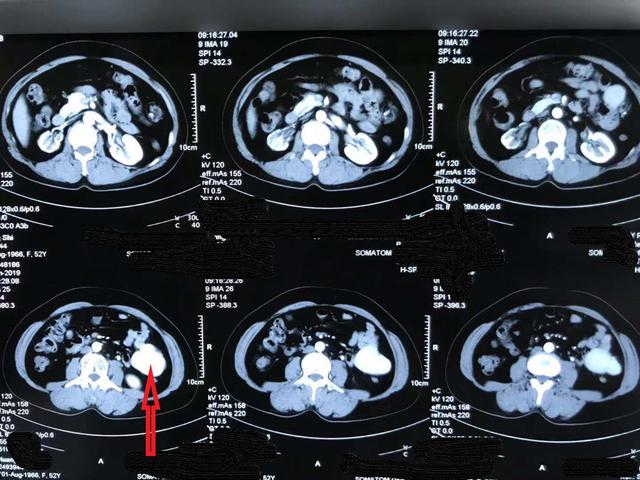

副脾ct图片

副脾显示清晰且与脾脏强化一致

证实为胰尾部异位脾脏 副脾是位于正常脾脏之外的与正常脾脏结构相似